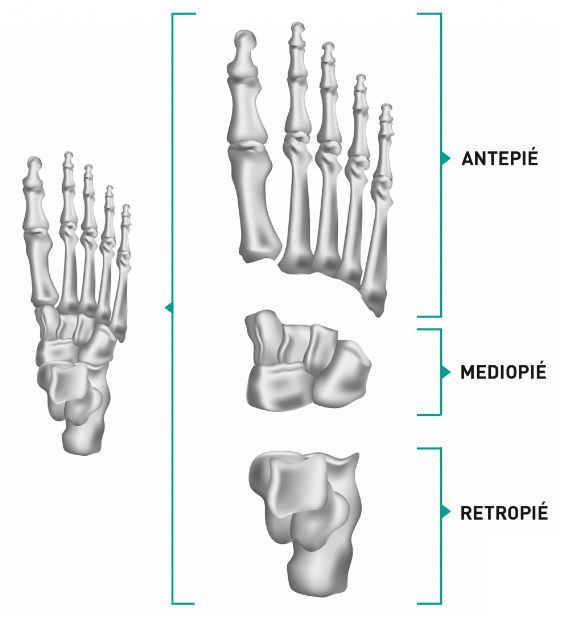

¿Sabes cuáles son los huesos del pie humano? El pie es una estructura compleja que está compuesta por 26 huesos. Estos huesos están dispuestos en tres secciones principales: el tarso, el metatarso y los dedos de los pies.

Cada sección tiene una función específica y está diseñada para soportar el peso del cuerpo y permitir el movimiento.

El tarso es la sección posterior del pie, y está formado por siete huesos que se articulan entre sí.

Principales huesos del pie

Estos huesos se dividen en dos grupos: el talón y el mediopié. El talón está compuesto por el calcáneo, el hueso más grande del pie, que soporta el peso del cuerpo al caminar o correr.

El mediopié (que se ubica justo antes de los dedos) está formado por el astrágalo, el hueso navicular, el cuboides y los tres huesos cuneiformes. Estos huesos se articulan entre sí para formar el arco del pie, que actúa como una estructura de absorción de choques.

El metatarso es la sección media del pie, y está formado por cinco huesos largos que se extienden desde el tarso hasta los dedos de los pies. Estos están diseñados para soportar el peso del cuerpo al caminar o correr, y son los principales responsables de la forma y la función del arco de los pies.

Dedos del pie

Los dedos de los pies están formados por un total de 14 huesos, llamados falanges. Cada dedo tiene tres falanges, excepto el dedo gordo del pie, que tiene solo dos. Estos están dispuestos en una serie de articulaciones que permiten el movimiento y la flexibilidad del pie.

Es importante tener en cuenta que los huesos del pie están interconectados y trabajan juntos para proporcionar estabilidad y movimiento. Cualquier problema en uno de ellos puede afectar la función general de los pies y causar dolor o incomodidad.

Sus partes

Cada hueso cumple una función específica y está diseñado para soportar el peso del cuerpo y permitir el movimiento.